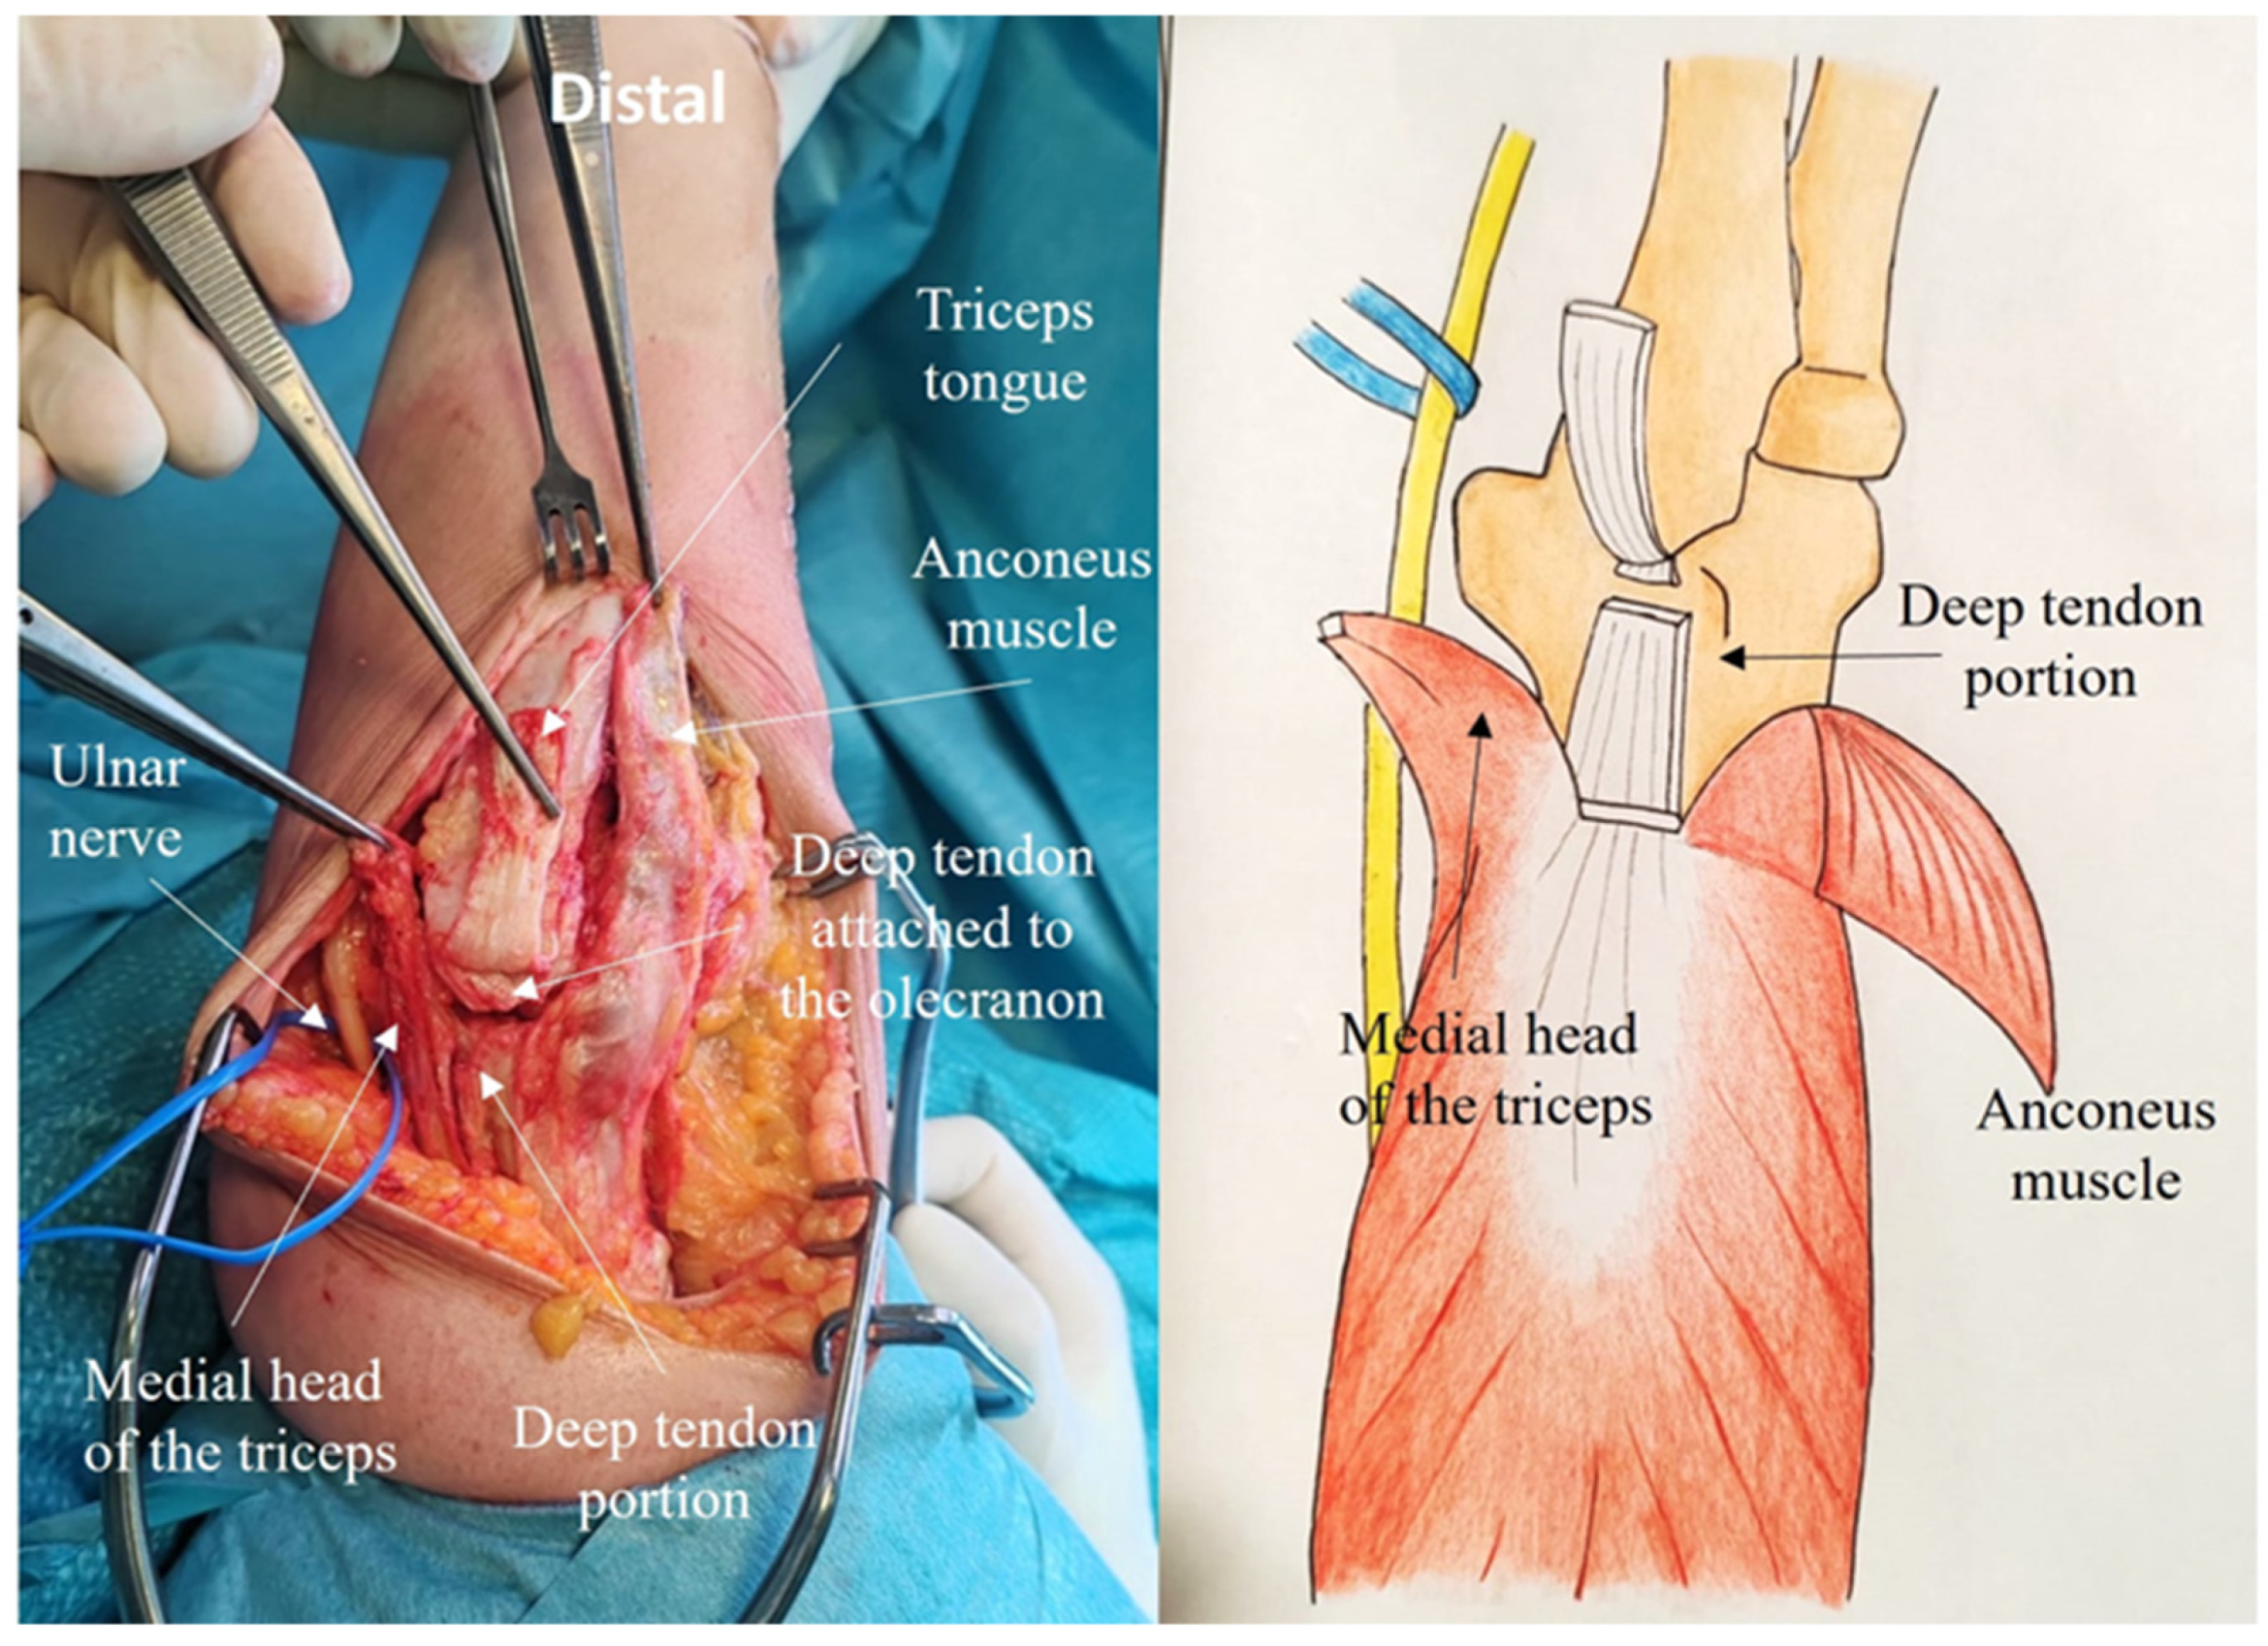

2.4. Development of the ARTT Approach